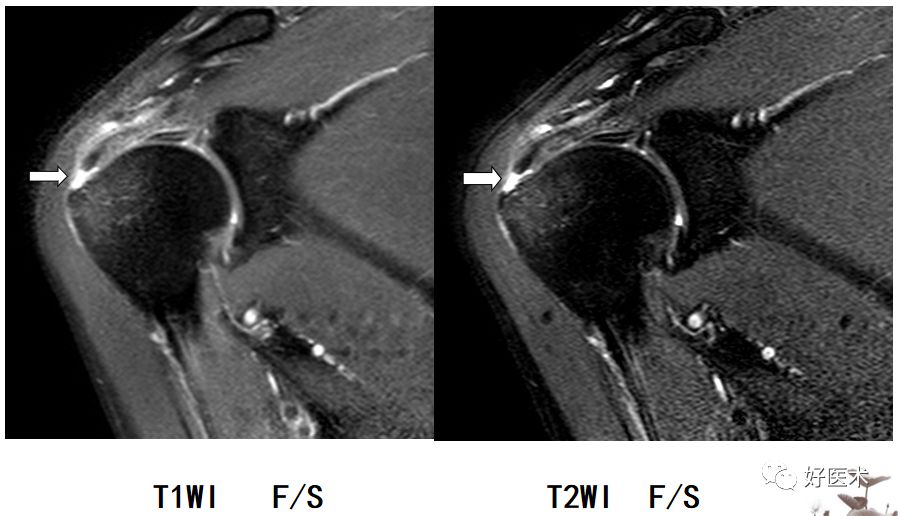

滑囊面部分撕裂冈上肌完全撕裂冈上肌全层撕裂伴肩撞(骨赘形成)冈上肌

冈上肌完全撕裂冈上肌全层撕裂伴肩撞(骨赘形成)冈上肌全层撕裂mri

mri提示冈上肌损伤,结合患者症状,查体诊断为:肩袖损伤